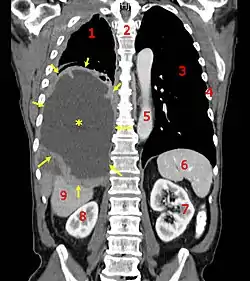

![]() الاشعة المقطعية الإكليلية مما يدل على ورم الظهارة المتوسطة الخبيثة

وسيلة الإيضاح: (الورم ★ الانصباب الجنبي المركزية)، 1 و3 الرئتين، 2 العمود الفقري، الأضلاع 4، 5 الشريان الأورطي، 6 الطحال، الكلى 7 و8 و9 الكبد. الاشعة المقطعية الإكليلية مما يدل على ورم الظهارة المتوسطة الخبيثة

وسيلة الإيضاح: (الورم ★ الانصباب الجنبي المركزية)، 1 و3 الرئتين، 2 العمود الفقري، الأضلاع 4، 5 الشريان الأورطي، 6 الطحال، الكلى 7 و8 و9 الكبد. | |